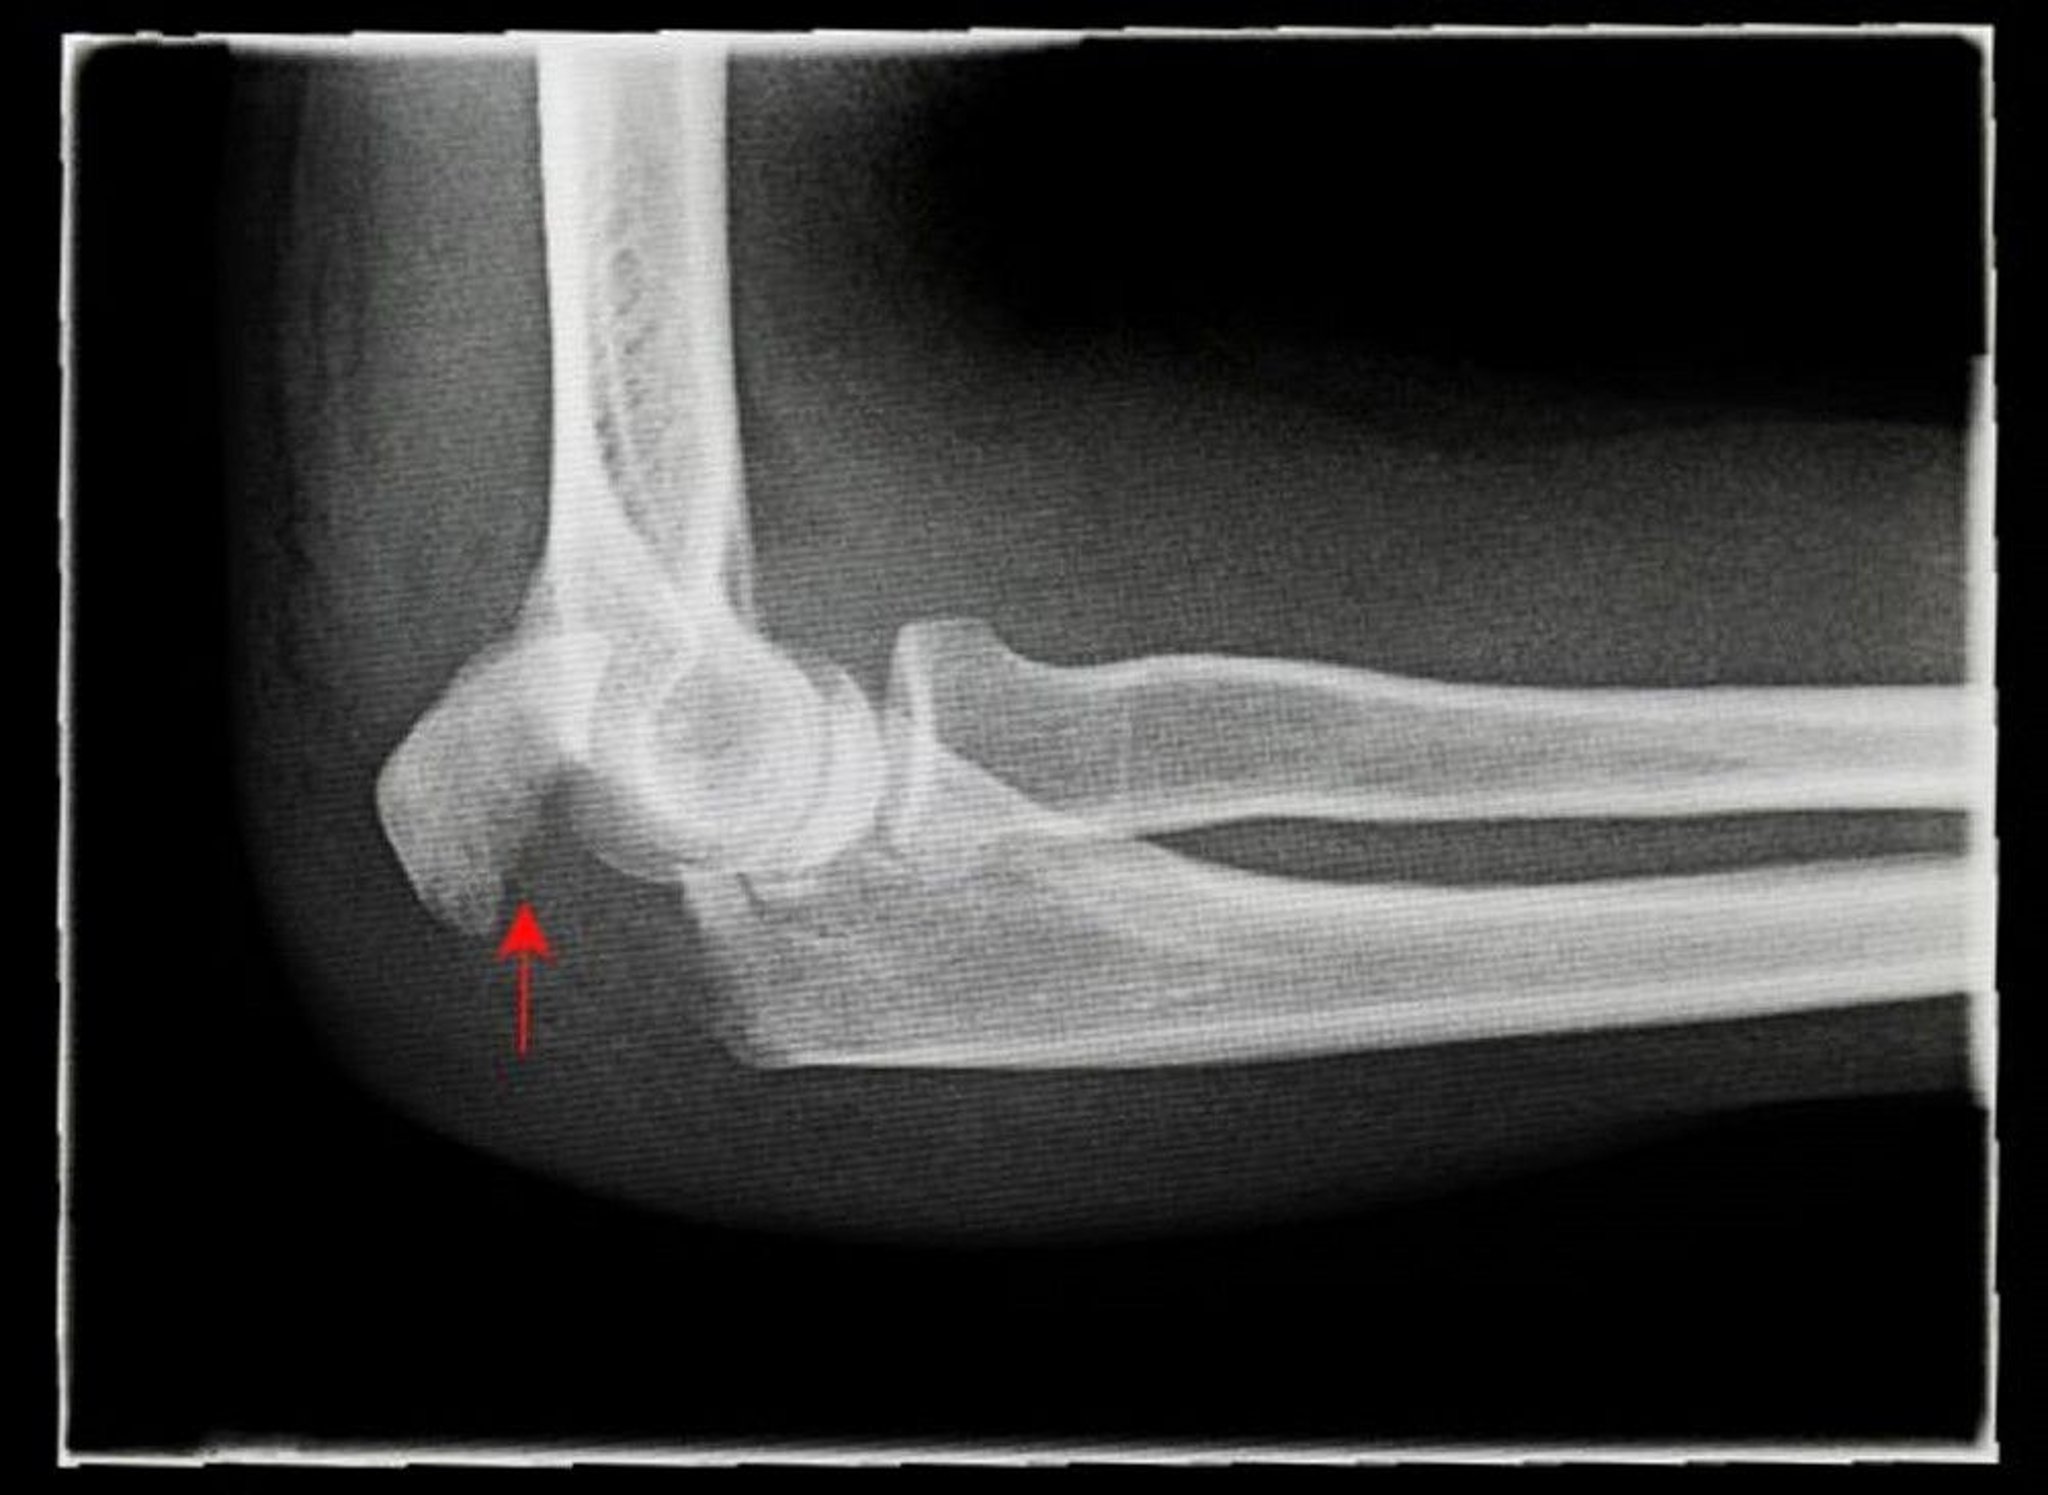

Olecranon Fracture

This lateral radiograph shows a displaced olecranon fracture (arrow).